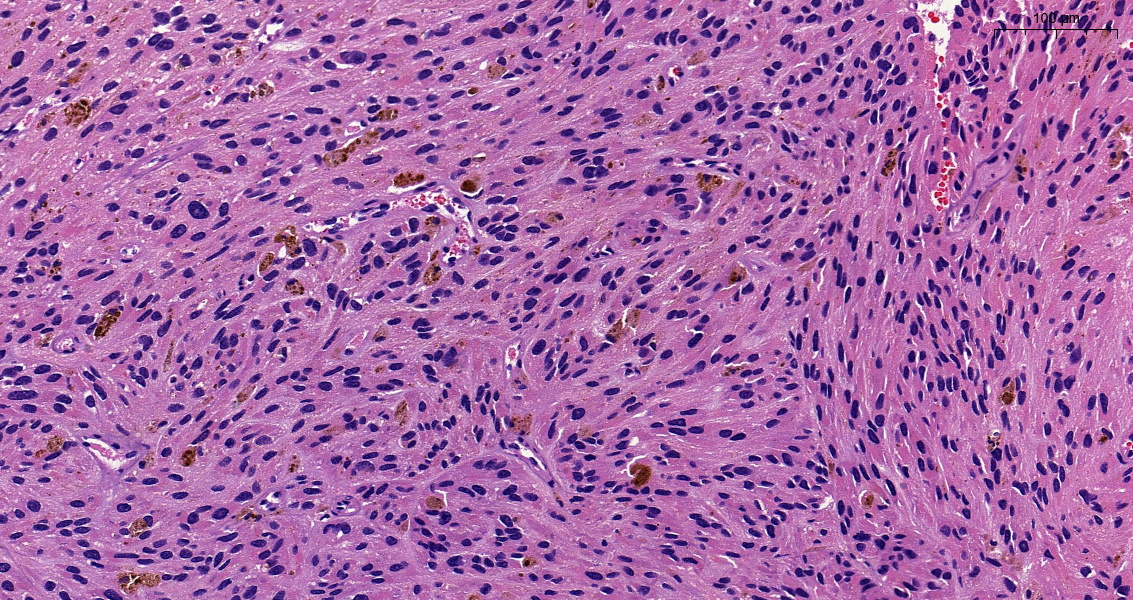

Incidental lung tumor... pulmonary hamartoma with unusual morphology?... what is your opinion? (2⃣) #PathTwitter #pulmpath @smlungpathguy @SansanoValero @yro854 @natasharekhtman @mkbaine @atman_ci @Path_Matt